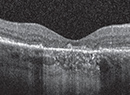

The Controversy of Band #2

What should we call the second of four outer retinal hyperreflective bands on OCT imaging?